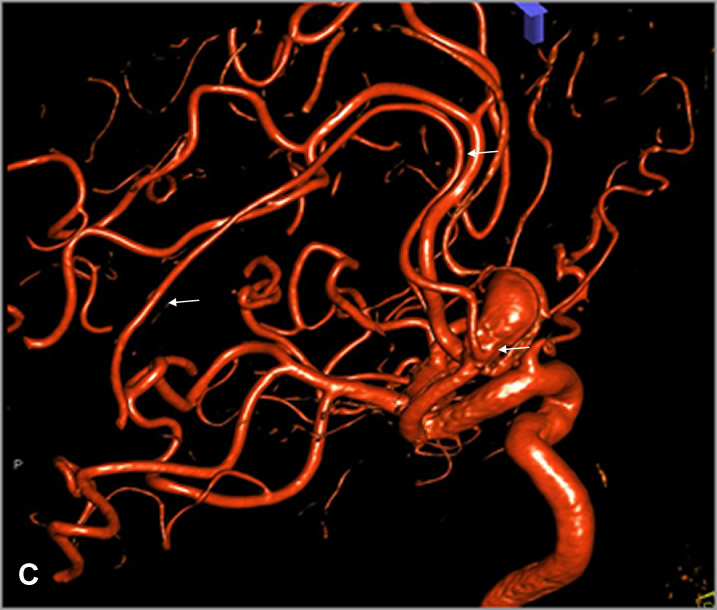

A, B: Series angiográficas en proyecciones AP y L de arteria carótida interna izquierda, observándose aneurisma de arteria comunicante anterior (flechas negras). C: Reconstrucción 3D. Nótese origen adyacente al cuello aneurismático y trayecto de arteria cerebral anterior accesoria (flechas blancas).

En 2017 sufrió traumatismo craneal leve en accidente de tráfico, motivando la realización de neuroimagen en la que se identificó un aneurisma de arteria comunicante anterior. Posteriormente se realizó arteriografía diagnóstica, confirmando la presencia de un aneurisma sacular polilobulado de arteria comunicante anterior, con diámetros aproximados de 13mm x 9 mm y cuello de 4 mm. Como variante de la normalidad, el paciente presenta además una duplicación del segmento A2 abarcando el trayecto pericalloso, evidente en las series angiográficas de arteria carótida interna izquierda, cuyo origen se encuentra en íntima relación con el cuello aneurismático, y que podría corresponder a una persistencia de la arteria mediana del cuerpo calloso (variante con una prevalencia de entre 3 y 6%1,2).